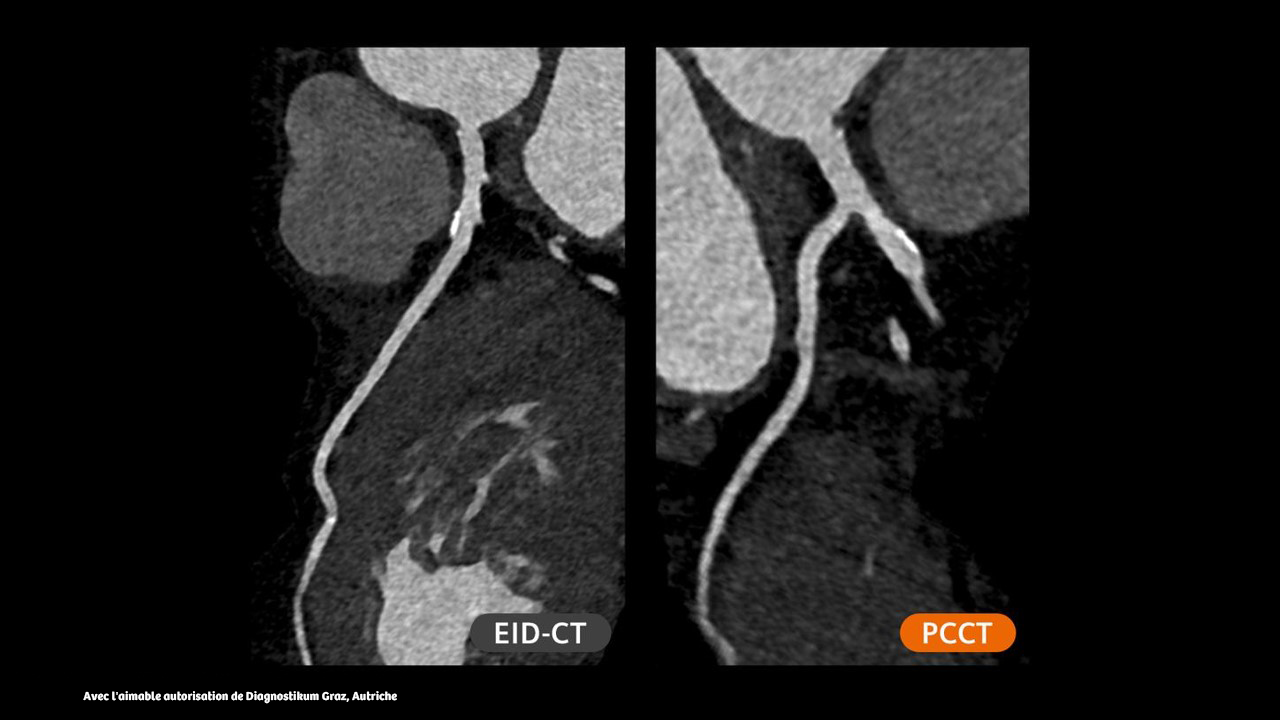

Les patients présentant des scores calciques élevés peuvent désormais être pris en charge avec un scanner à comptage de photons et bénéficier de l'imagerie cardiaque de la technologie Quantum avec des artéfacts de décalage réduits.

L'épaisseur de coupe unique de 0,2 mm du NAEOTOM Alpha.Prime avec Quantum HD offre une grande précision en neurologie et peut aider à optimiser les diagnostics des patients : évaluation de l'accident vasculaire cérébral, anévrisme, fistule veineuse du LCR (voir les images ci-dessus) ou oreille interne.